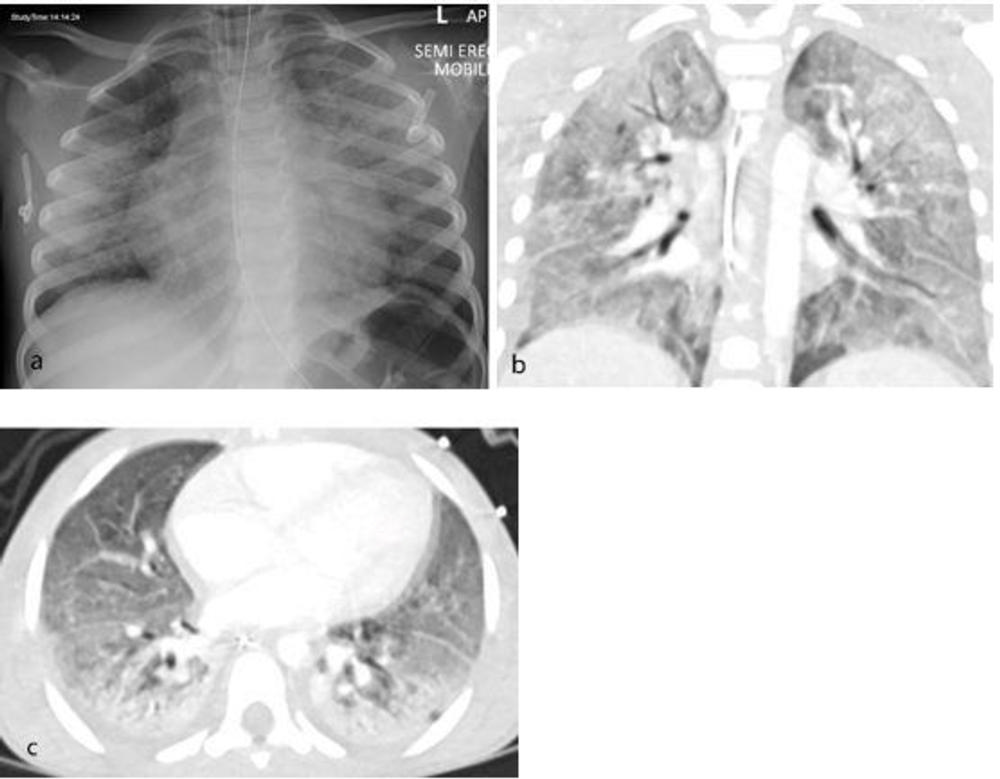

All 35 children underwent chest X-ray due to fever, sepsis or features of multisystem inflammation. Nineteen X-rays were abnormal, the most common finding being that of bronchial wall thickening.

The predominant findings on chest CT were basal consolidation, or part of the lung filling with fluid; and collapsed lung with pleural effusions, or build-up of fluid in the outer membranes of the lungs.

Figure 2. Thoracic findings in a 5-year-old boy with Multisystem Inflammatory Syndrome in Children (MIS-C). (a) Chest radiograph 4 days after admission shows perihilar bronchial wall cuffing and interstitial thickening with hazy surrounding airspace consolidation extending towards the peripheries. (b, c) Coronal and axial contrast-enhanced CT chest 1 day after the radiograph shows diffuse bilateral airspace consolidation with an anteroposterior gradient suggestive of acute respiratory distress syndrome (ARDS).